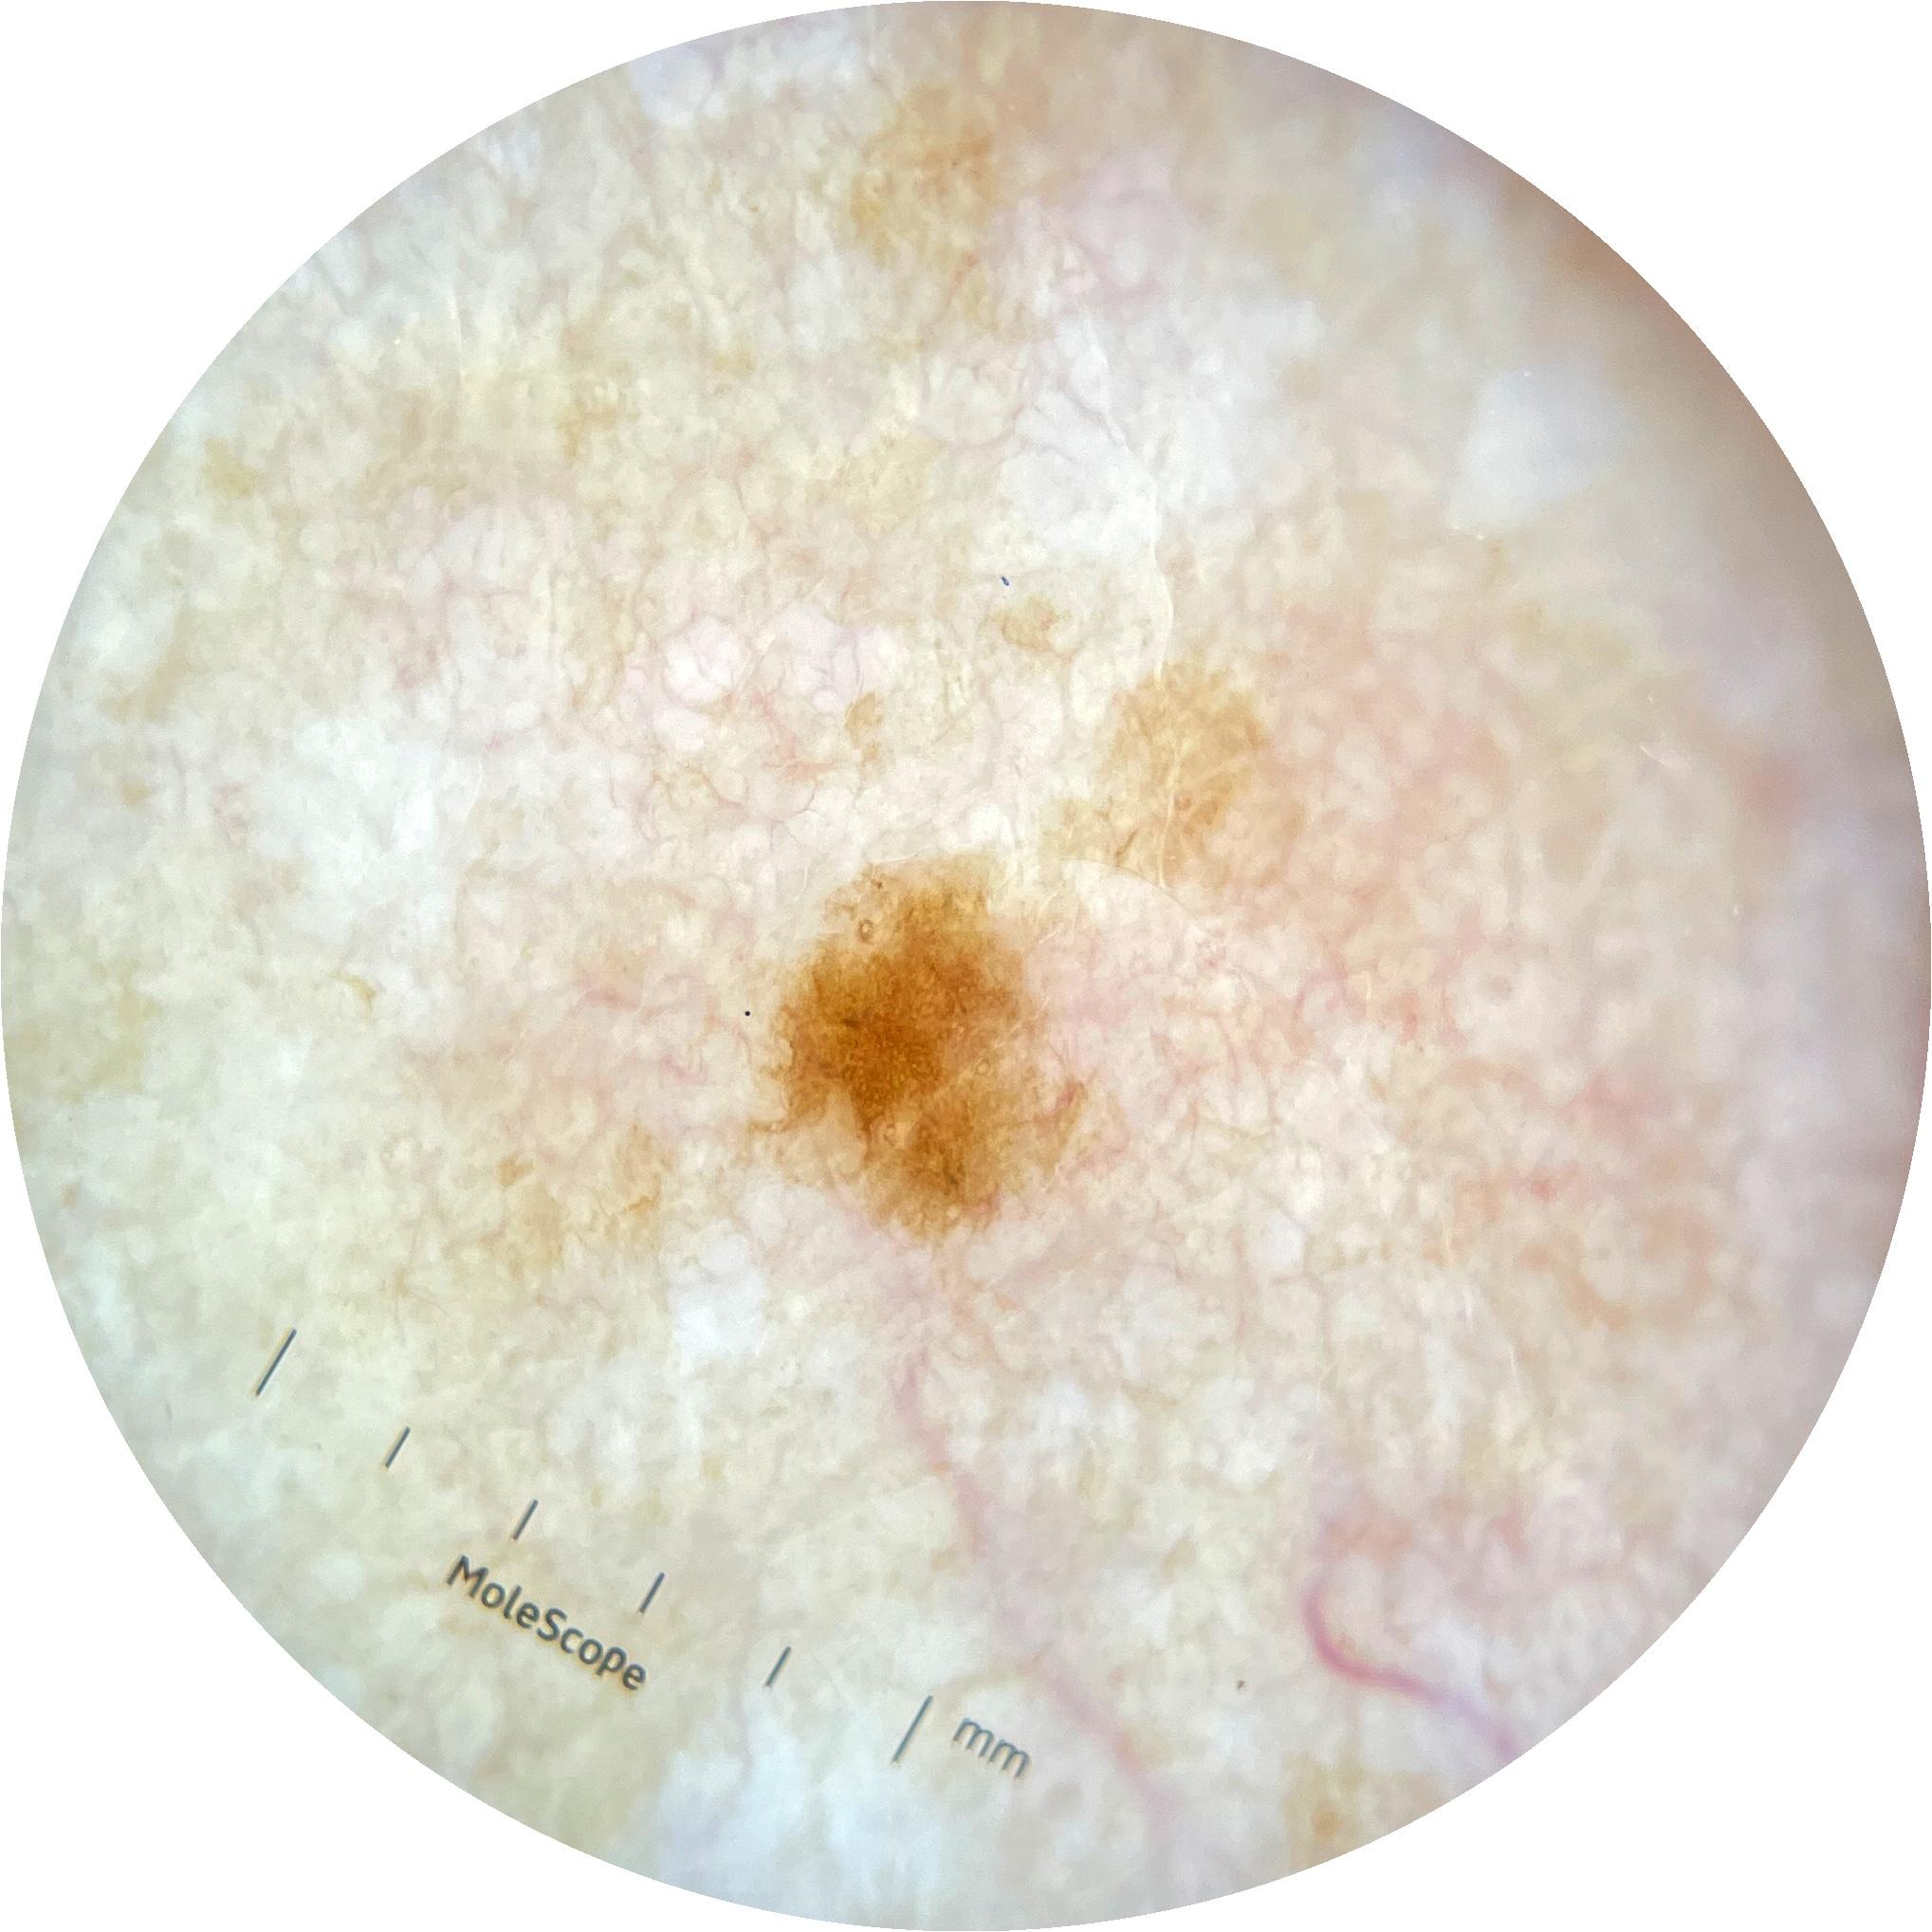

ISIC_9097190

2049 x 2049

acquisition_day 181

age_approx 45

anatom_site_1 Trunk

anatom_site_2 Anterior trunk

anatom_site_general anterior torso

diagnosis_1 Benign

image_type dermoscopic

personal_hx_mm True